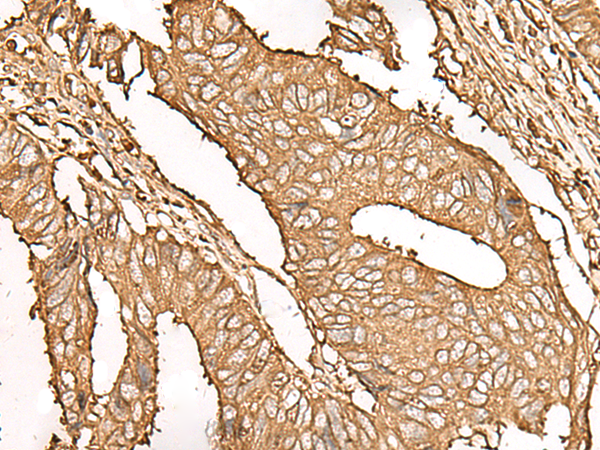

IHC positive control: |

Human cervical cancer and Human colorectal cancer |

IHC Recommend dilution: |

50-300 |